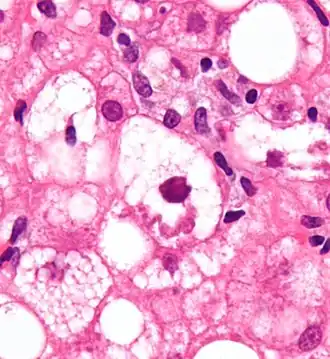

Micrograph showing a Mallory body. Original magnification 400X. H&E stain. -